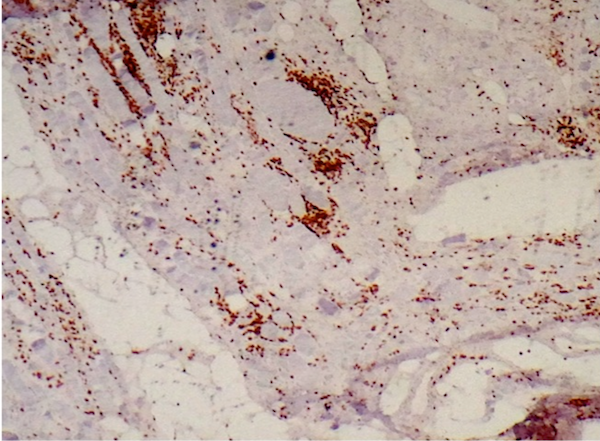

- There can be a brisk inflammatory response including CD8+ lymphocytes, which may invade non-necrotic myofibers

- Occasional myofibers undergoing phagocytosis by CD68+ macrophages can be identified

- CD8+ T lymphocytes highlight the inflammatory response and infiltrate non-necrotic myofibers